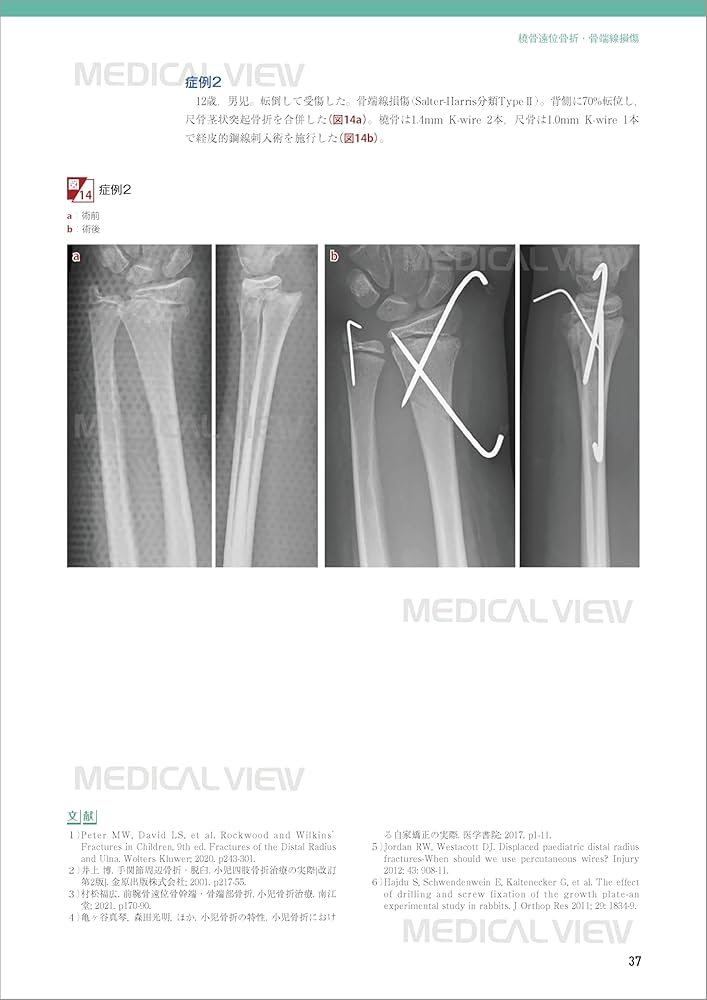

裁断済みです。書き込み、マーカーなし。「新OS NEXUS No.15 小児の骨折と手術」企画・編集 大谷 卓也定価 13,200円(税込) (本体12,000円+税)A4判 168ページ オールカラー,イラスト200点,写真100点2025年8月3日刊行